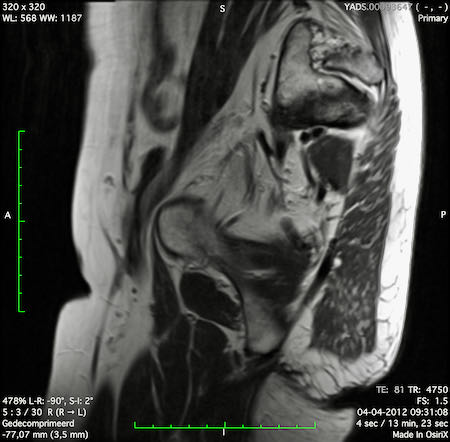

Hình ảnh

Các hình ảnh được cung cấp cho thấy ung thư biểu mô tế bào nhẫn với tình trạng dày lan tỏa thành trực tràng, hình ảnh bia bắn điển hình, và sự xâm lấn mỡ mạc treo trực tràng.